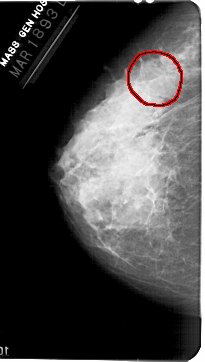

A_1361_1.LEFT_CC

LEFT_CC LINES 5416 PIXELS_PER_LINE 3061 BITS_PER_PIXEL 12 RESOLUTION 43.5 OVERLAY

FILE: A_1361_1.LEFT_CC.OVERLAY

TOTAL_ABNORMALITIES 1

ABNORMALITY 1

LESION_TYPE MASS SHAPE IRREGULAR MARGINS OBSCURED

ASSESSMENT 3

SUBTLETY 1

PATHOLOGY BENIGN

TOTAL_OUTLINES 1

BOUNDARY